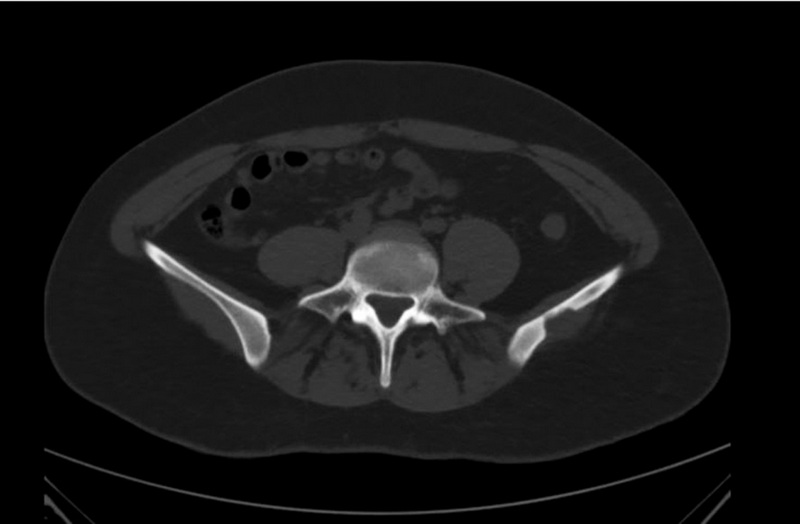

Diagnosis of solitary eosinophilic granuloma by CT, MRI, and 18F-FDG PET/CT: two clinical cases

This paper presents two clinical cases of eosinophilic granuloma of bone diagnosed by CT, MRI, and 18F-FDG PET/CT. In both cases the patients were admitted to the clinic with suspected primary malignant bone tumor and the diagnosis of a solitary eosinophilic granuloma was made based on the results of comprehensive radiological diagnostic examination and histological verification. Solitary eosinophilic granuloma of bone is an infrequent condition, occurring in less than 1% of cases of skeletal tumor masses. The most common eosinophilic granuloma is found in the parietal and frontal bones of the skull and is an osteolytic volumetric mass that gradually increases in size. Although most bone tumors can be detected by radiography, computed tomography is preferred, primarily because of its superior ability to detect cortical bone destruction. The diagnostic accuracy of computed tomography and magnetic resonance imaging may be different. The combined use of radiological and radionuclide methods allows us to narrow the spectrum of differential diagnosis. Unfortunately, relatively low specificity of existing radiological diagnostic studies in most cases does not allow to establish a precise diagnosis, and biopsy with subsequent pathological examination remains the method of choice. These clinical observations demonstrate the need to include eosinophilic granuloma in the differential diagnosis when a solitary osteolytic focus is detected.